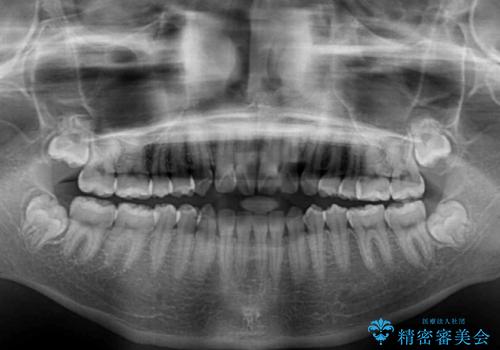

話しにくいオープンバイト ワイヤー装置による抜歯矯正治療

- 前歯のオープンバイトを気にして来院された患者様です。

上下前歯の前後位置が大きくずれていたため、上顎左右第一小臼歯2本を抜歯してワイヤー装置による矯正治療を行うこととしました。

オープンバイトの原因は舌の突出癖であり、癖が改善されないと治療経過に影響を及ぼすため、舌のトレーニングを指示しました。